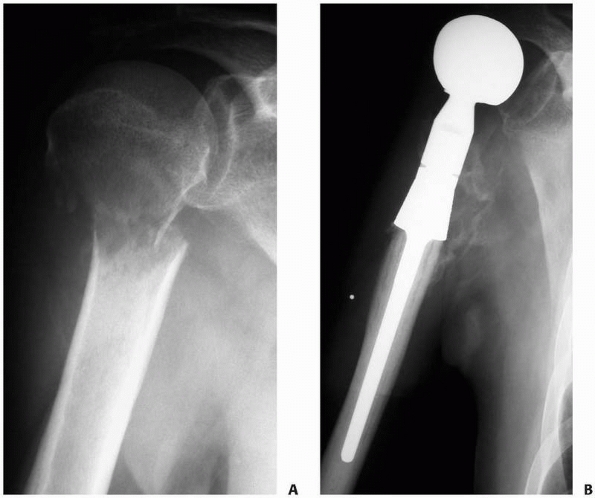

FIGURE 20-4 A.

Anteroposterior radiograph of the right proximal humerus in a 54-year-old man with multiple myeloma. He has a displaced fracture through the humeral neck with a large lytic lesion filling the proximal humerus. B. Postoperative radiograph after resection of the proximal humerus and modular prosthetic replacement. The stem is cemented into the native humerus. Excellent pain control was achieved with this reconstruction. |